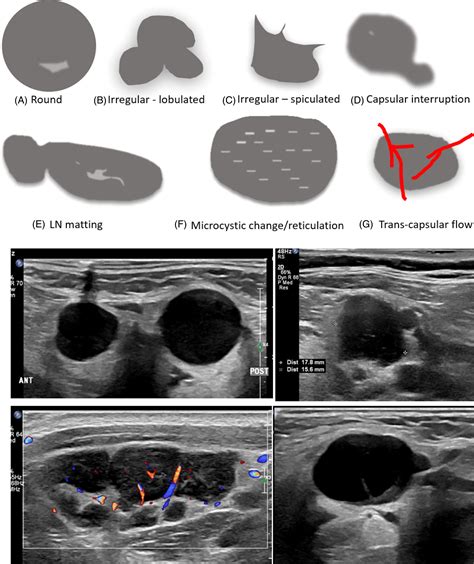

• Size and shape of the lymph node.

• Internal architecture, such as the loss of a fatty hilum.

• Cortical thickness, which is a major factor in diagnostic assessment.

• Vascularity, or how blood flows within the node.

The primary goals are to assess whether the node is reactive or suspicious. Reactive nodes are usually oval-shaped, maintain a normal fatty hilum, and exhibit healthy blood flow. In contrast, nodes suspicious for malignancy often appear round, show thickened cortices, and demonstrate abnormal vascular patterns.